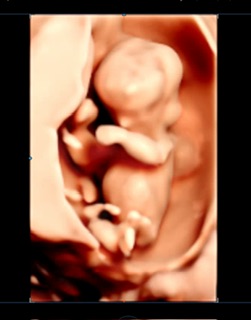

질문이 있어 글을 남겨봅니다.

내일은 2차 기형아 검사 하러 가는 날인데

1차 기형아 검사하러 갔다가

2차 때는 취약x증후군 검사도 권유를 하길래

선택권 있는 검사인지 물어보니

산모가 고민해보고 선택 해도 되는 거라고 했습니다.

인터넷에 찾아보니 중요한 검사는

아닌 거 같긴 한데 해야 할지 안해도 될지

고민 되어 글을 남겨 봅니다:)